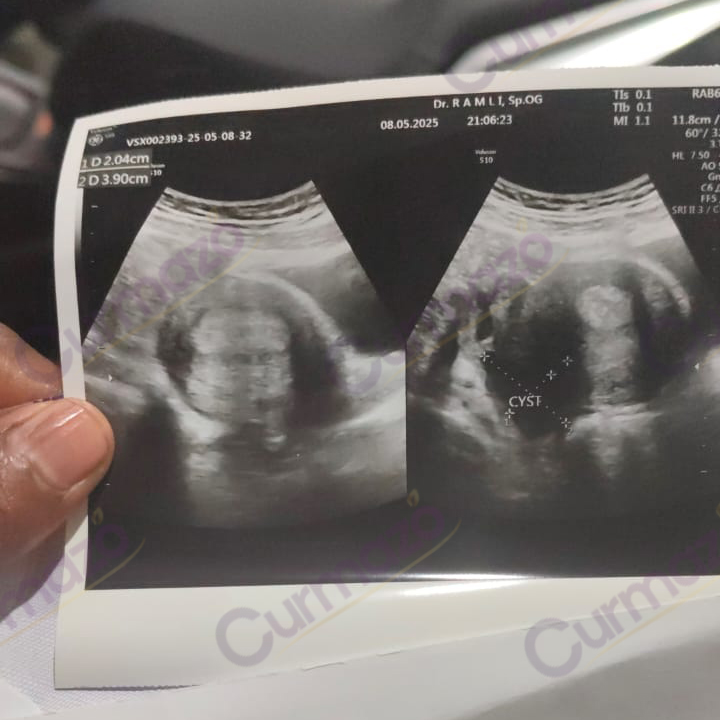

20 Maret 2025, saya periksa ke dokter ternyata ada kista di kanan kiri sebesar 6 cm. Saya menolak dioperasi karena tidak mau diangkat kantung rahimnya.

Setelah 1 bulan konsumsi, saya sudah tidak merasakan nyeri sampai tulang belakang, dan nafsu makan saya meningkat. 8 Mei 2025 saya periksa lagi, hasilnya kista 6 cm di kiri hilang total dan yang di kanan mengecil dari 6 cm jadi 2 cm.

Foto hasil USG before:

Foto hasil USG after: